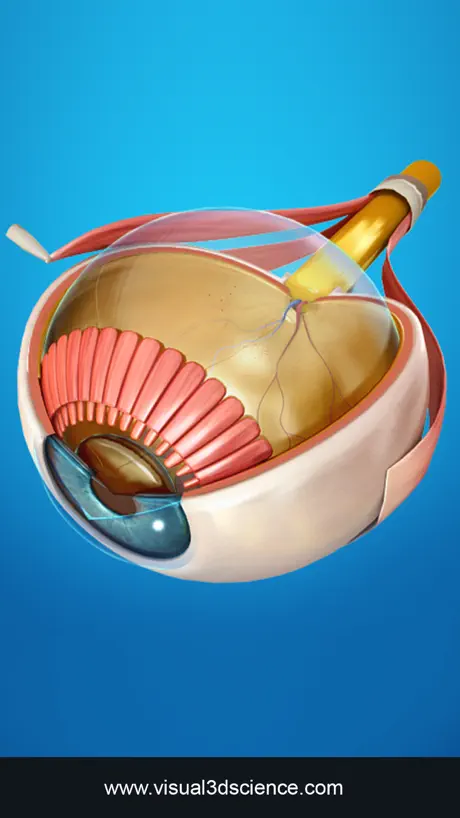

Screenshots